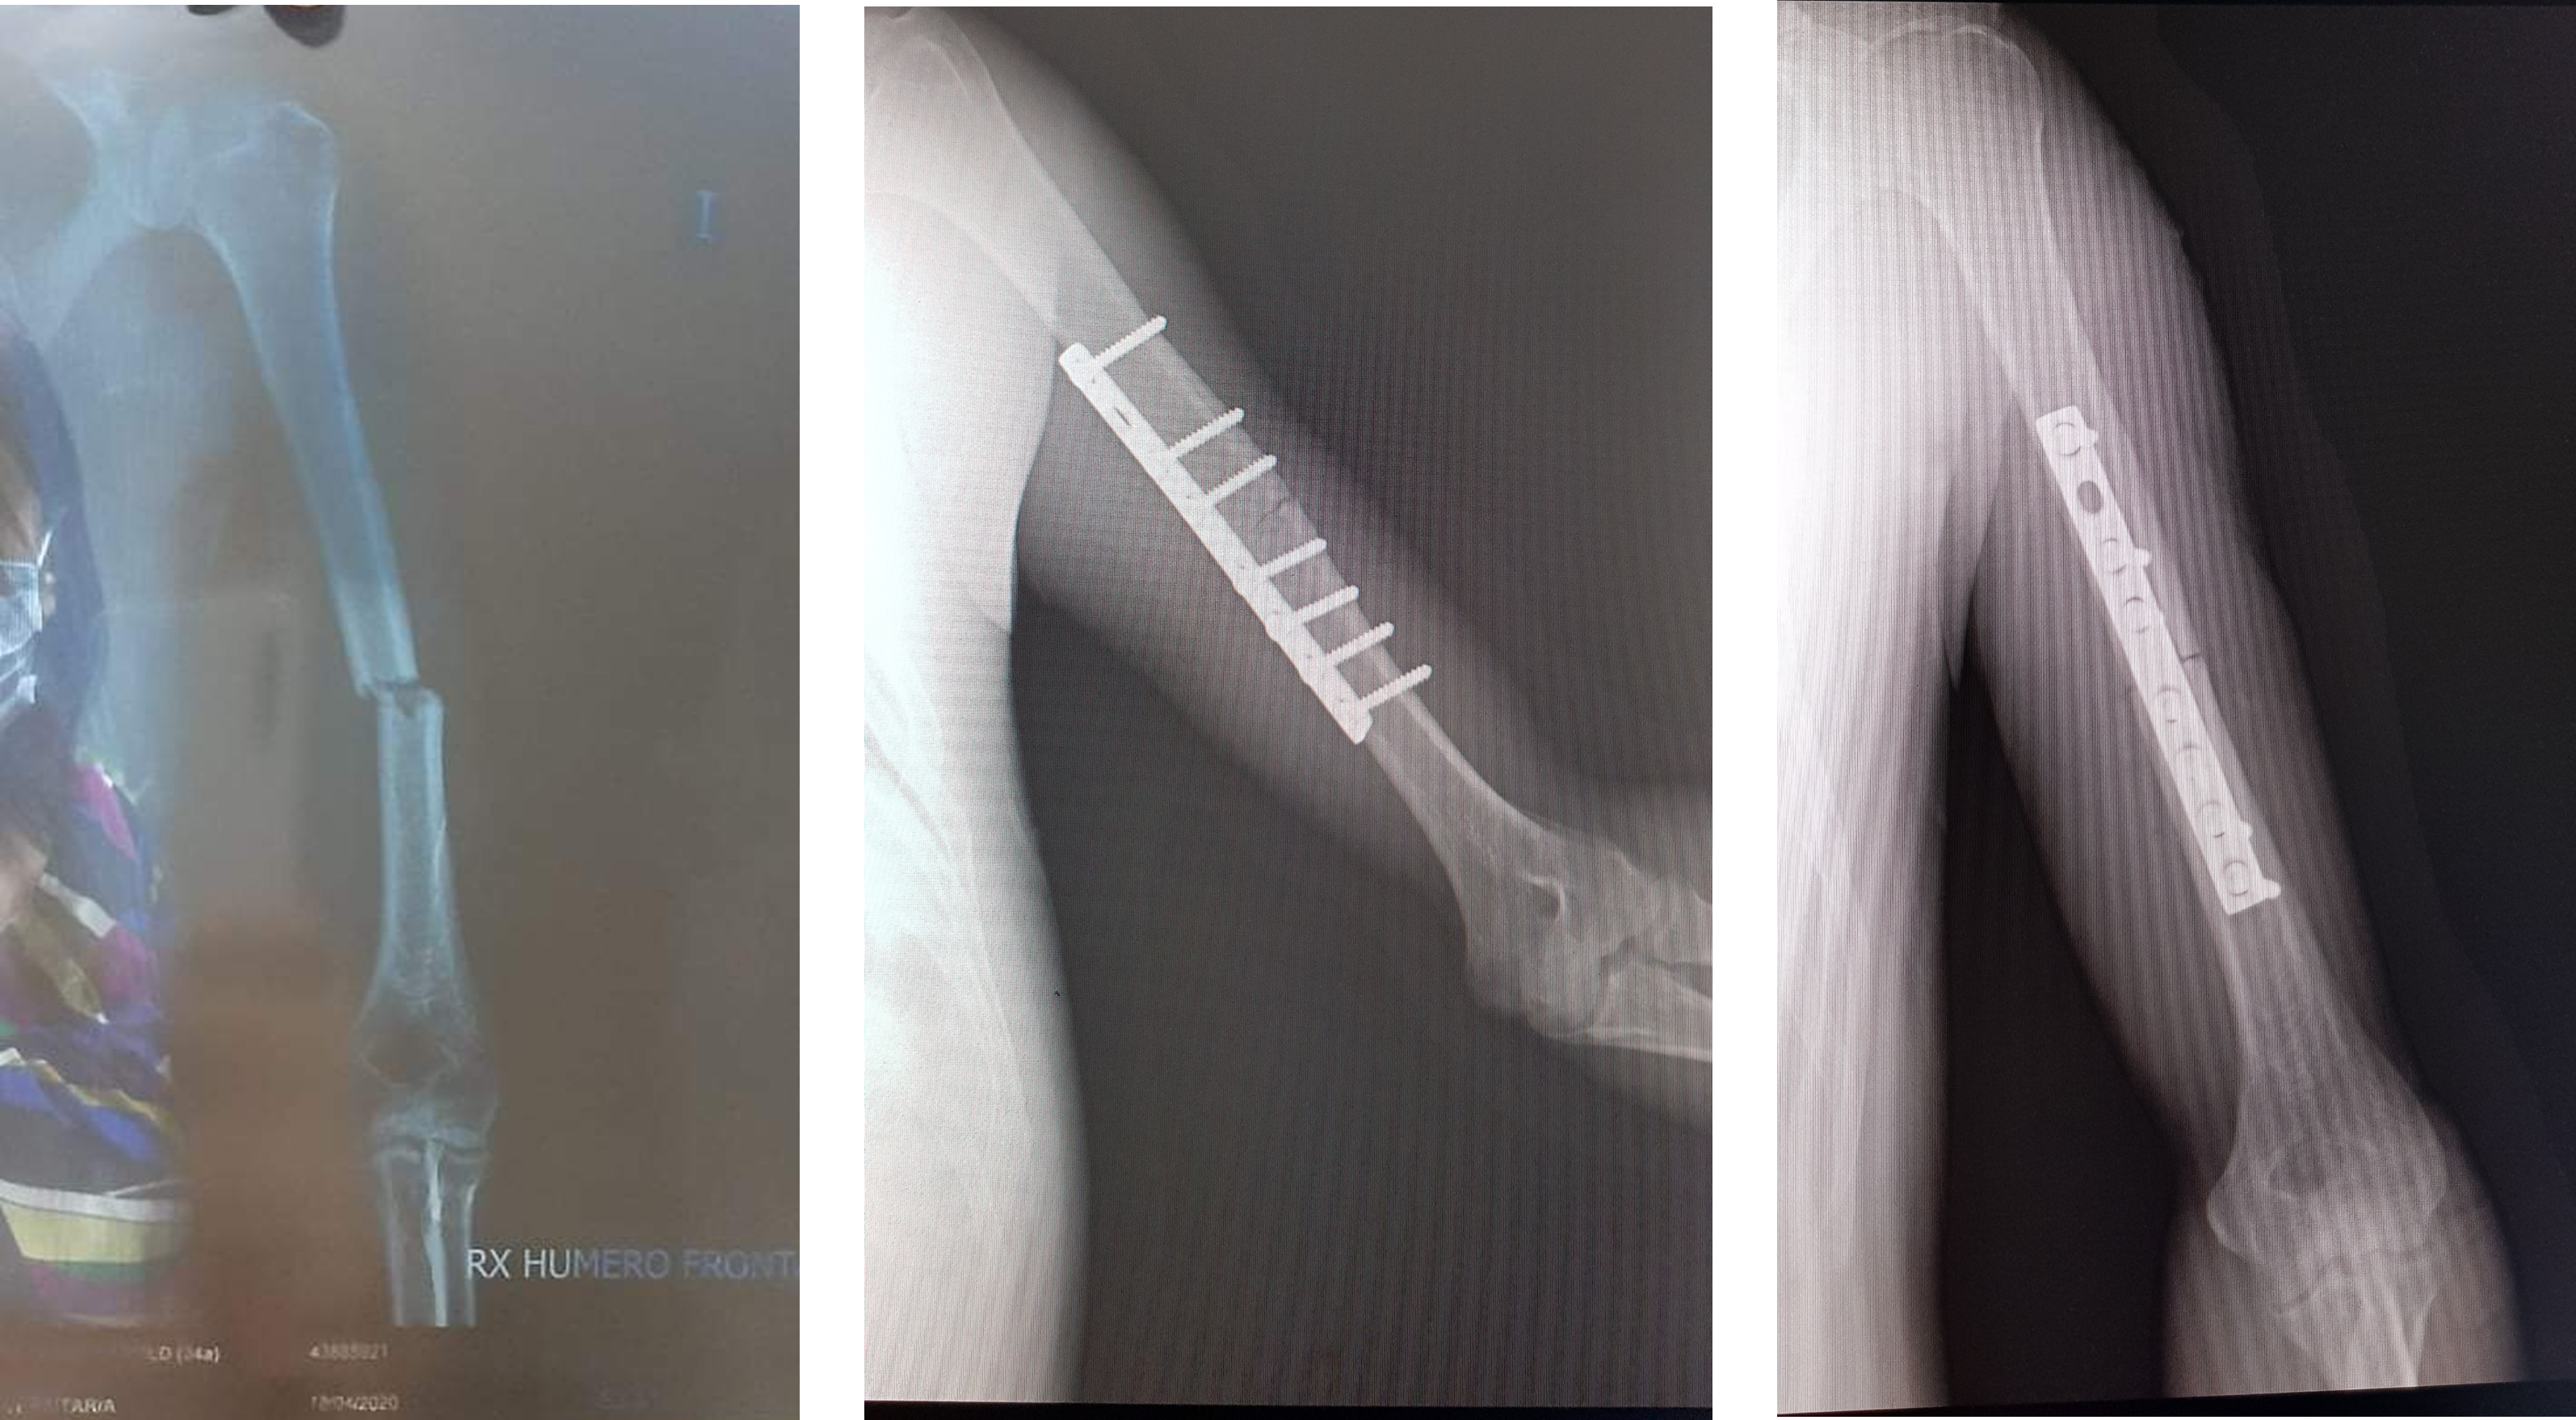

Paciente varón de 34 años de edad con antecedente de caída en vía pública. Cae al resbalar sobre piso mojado mientras usa sandalias. Dx fractura de húmero diafisiario izquierdo el día 18/04 operado el 07/05 del mismo año.